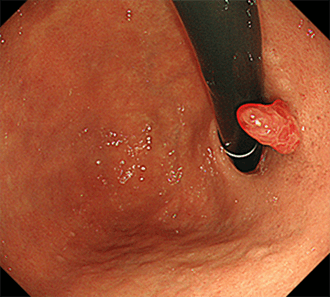

胃底腺ポリープは、主に胃液を分泌する胃底腺の細胞が増殖したものです。ピロリ菌に感染していない胃に見られることの多い、元気の証拠のようなポリープとされています。がん化は非常にまれではありますが、巨大なものになるとがん化のリスクが上昇してきます。プロトンポンプ阻害薬(PPI)・P-CABといった胃酸を強力に抑える酸分泌抑制薬を用いていると、血中のガストリンが増加し、それが胃底腺ポリープの発生・増大の原因となることがあります。

胃底腺ポリープ

胃底腺ポリープはこのように多発することが多いです。過形成性ポリープ(腺窩上皮型過形成ポリープ)は、胃の粘膜表面の被蓋上皮が、間質の血流増加を伴って増殖したものです。

胃腺腫胃カメラ(胃内視鏡検査)の施行時に、偶然みつかることがほとんどです。健診・胃がん検診でのバリウム検査が、発見契機になることも多いです。胃底腺ポリープや過形成ポリープのほとんどは、内視鏡観察での鑑別が可能です。胃底腺ポリープは周囲粘膜と同じ色調の、つるつるとした無茎性~亜有茎性の数mm程度のことが多い病変です。対して過形成ポリープは赤みの強いやや凹凸のある表面をした、亜有茎性~有茎性のこともあるポリープです。胃底腺ポリープではがん化は非常にまれで、過形成ポリープでも通常は2cmを超えない場合での担がんは比較的まれです。しかしながら小さくても形態からラズベリー様腺窩上皮型胃腫瘍(ラズベリー型胃がん)との鑑別を要すことがあります。そのため通常は胃底腺ポリープ・過形成ポリープでは生検での組織病理学的検査を要することは少ないですが、上記のような場合や、家族性大腸腺腫症(FAP)に生じる胃底腺ポリープなどではがん化していないかをみるために、生検を要することがあります。